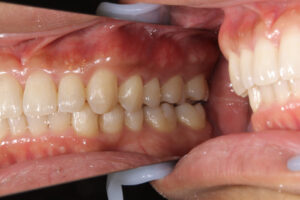

2年前からインビザラインして今月終了したが、上顎全体が前に出ているのと、下顎が後退しているのが気になる。

他に医院ではミニスクリューを勧められた。歯を抜かずに矯正しているため、イーラインが前に出ている。

4番抜歯をしないと治らない。しかも、奥歯が噛んでいない。ワイヤーによる全顎矯正が必要。